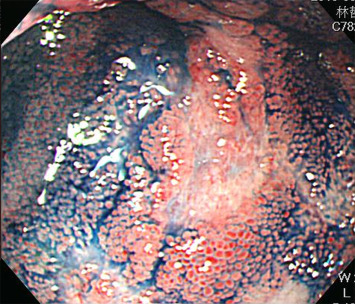

An esophagogastroduodenoscopy (EGD) showed erosive esophagitis, Los Angeles classification Grade A, and gastritis over antrum. An abdominal computed tomography (CT) showed an edematous change of the intestinal wall and the distal part of the ileum (Fig. 2 ). Empiric antibiotics with ciprofloxacin were prescribed for possible ileitis. A retrograde single balloon enteroscopy (SIF-260, Olympus Medical Systems, Tokyo, Japan) revealed several 0.5–1.5 cm discrete shallow ulcers and hyperemic mucosa at the distal ileum. The middle, proximal, and terminal ileum and the ileocecal valve to the rectum were not affected (Fig. 3 ). Chromoendoscopy with 0.2% indigo carmine dye demonstrated edematous hyperemic intestinal villi (Fig. 4 ). An endoscopic biopsy specimen of ileal ulcers showed chronic inflammation. The creatinine level was 76.9 μmol/L (normal range 61.88–106.08 μmol/L). The platelet level was 379 × 103 /μL (normal range 150–450 × 103 /μL).

Chromoendoscopy with 0.2% indigo carmine dye demonstrates edematous hyperemic ...

Chromoendoscopy with 0.2% indigo carmine dye demonstrates edematous hyperemic intestinal villi.